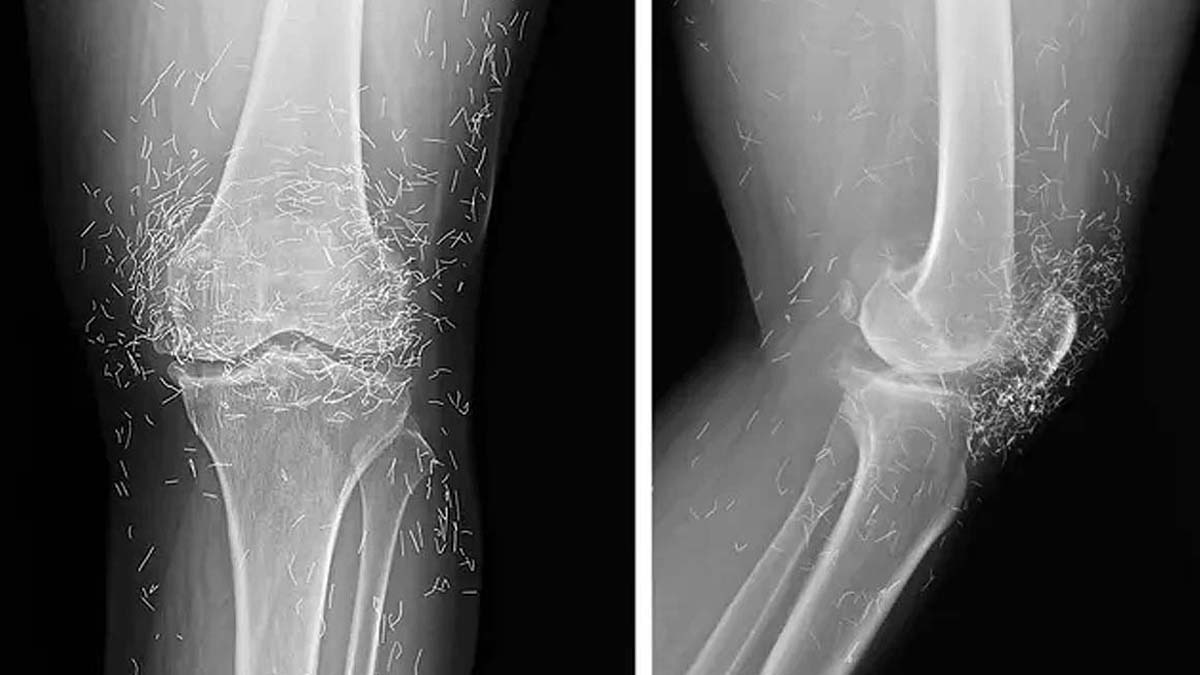

महिला ने हफ्ते में कई बार एक्यूपंक्चर करवाया, खासकर जब दर्द ज्यादा होता. बाद में, जब दर्द असहनीय हुआ, वह अस्पताल गई. डॉक्टरों ने घुटने का एक्स-रे किया, जिसमें चौंकाने वाला नजारा दिखा. घुटने की हड्डी (शिनबोन और थाईबोन) मोटी और सख्त हो गई थी. वहां 'बोनी स्पर्स' (हड्डी के उभार) थे. लेकिन सबसे हैरानी की बात थी सैकड़ों छोटे-छोटे सोने के तार, जो घुटने के आसपास दिखे.

डॉक्टरों को पता चला कि ये तार एक्यूपंक्चर का हिस्सा थे. यह 'गोल्ड-थ्रेड एक्यूपंक्चर' तकनीक थी, जिसमें छोटे, स्टराइल सोने के तार जानबूझकर टिश्यू में छोड़ दिए जाते हैं ताकि लगातार स्टिमुलेशन मिले. यह एशिया में ऑस्टियोआर्थराइटिस और रूमेटॉयड आर्थराइटिस के लिए आम है.

तारों से एक्स-रे पढ़ना मुश्किल होता है. MRI कराना खतरनाक है क्योंकि धातु हिलकर नसों को नुकसान पहुंचा सकती है. तारों को एक्स-रे में ट्रैक करना आसान है, लेकिन डॉक्टरों ने चेतावनी दी कि इसके जोखिमों को समझना जरूरी है.